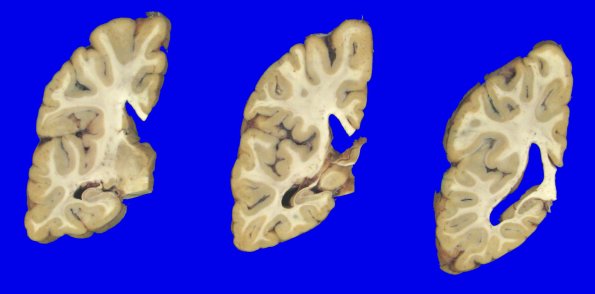

1A4 NCL (Case 1) gross 6

The cortical ribbon of the occipital lobe appeared thinned in foci.